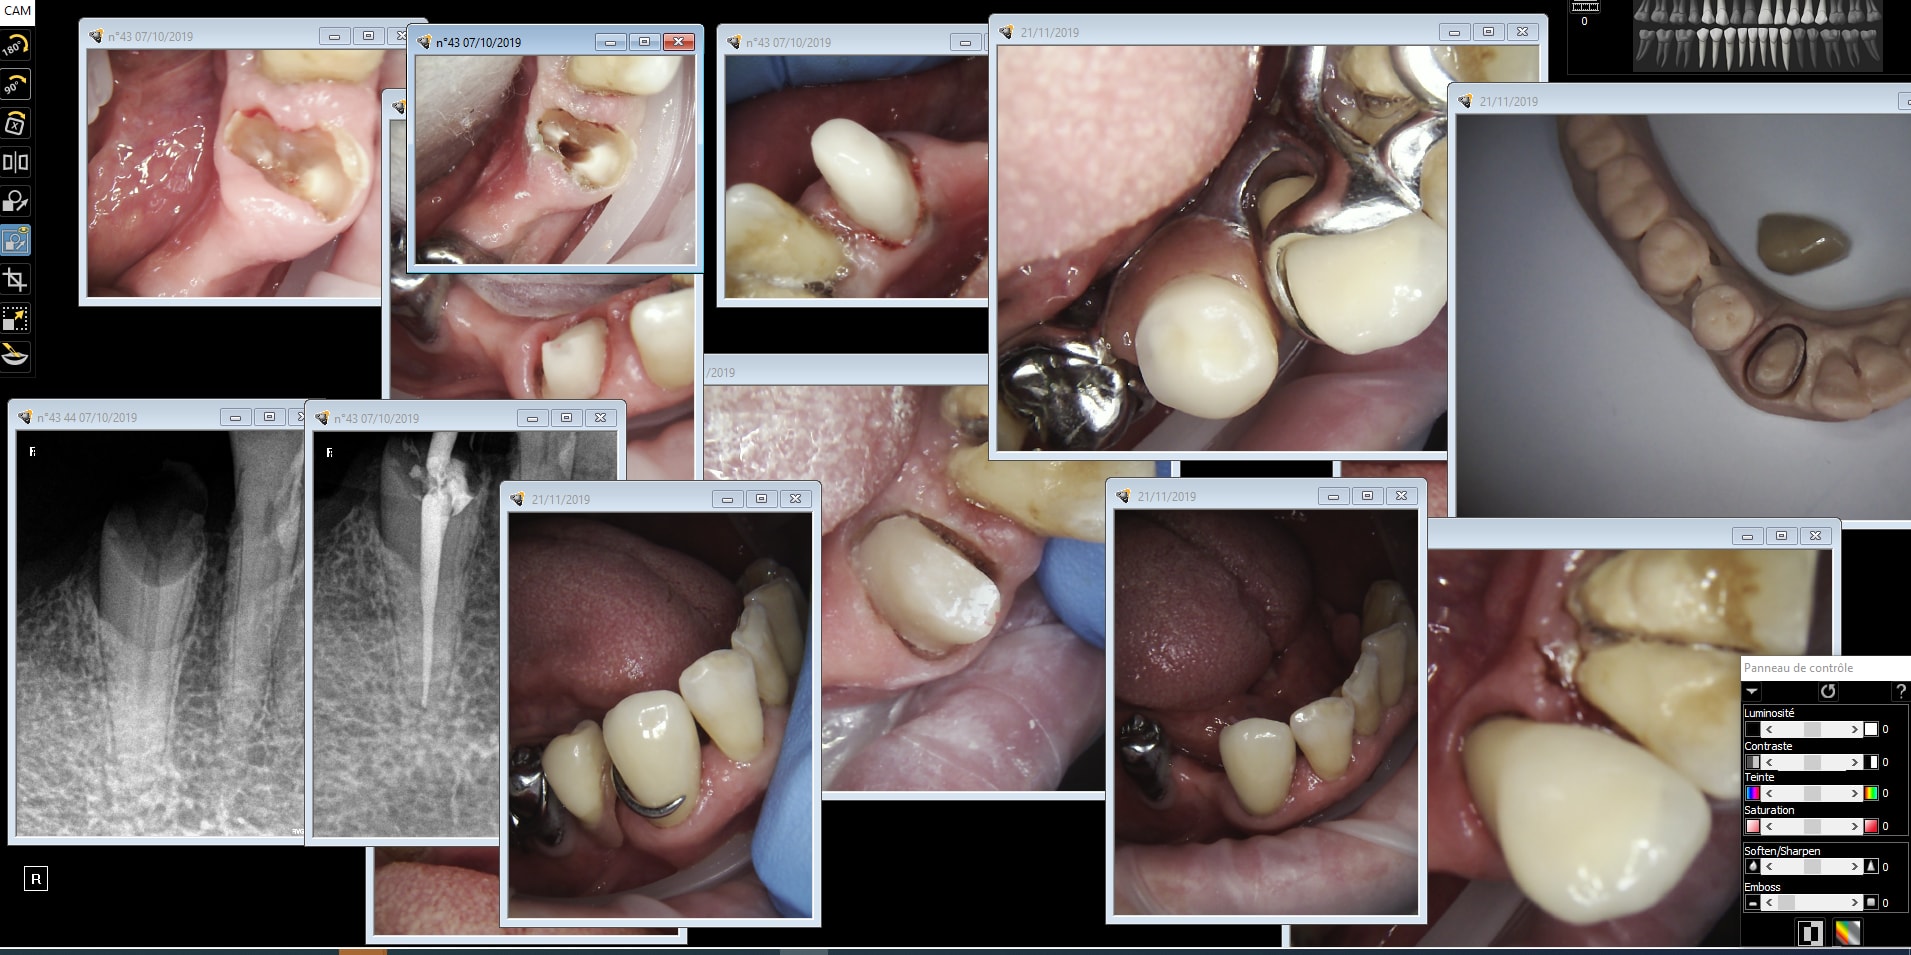

Aba 33 xmlb0d - Eugenol

Aba 43 vzub9x - Eugenol

Aba43 obh8cm - Eugenol

Abal 4 nmmt1w - Eugenol

Abal43 j7pu57 - Eugenol

Abal 43 slwjum - Eugenol